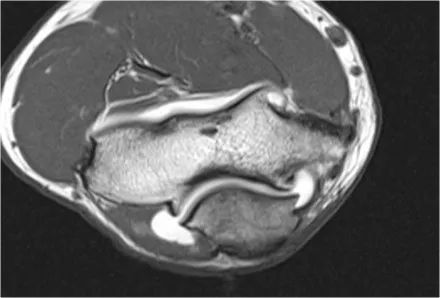

2.假游离体另一个常见的发现是你在矢状图上看到的一小块脂肪,看起来像一个小游离体或软骨缺失。如果我们观察鹰嘴的关节面,可以解释这一点。鹰嘴通常有两片软骨,中间有一小块软骨,里面充满了脂肪。